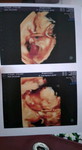

semoga tumbuh sehat , tidak kurang 1 apa pun , jadi anak pinter , anak baik , anak soleh .

Silversemoga tumbuh sehat , tidak kurang 1 apa pun , jadi anak pinter , anak baik , anak soleh .